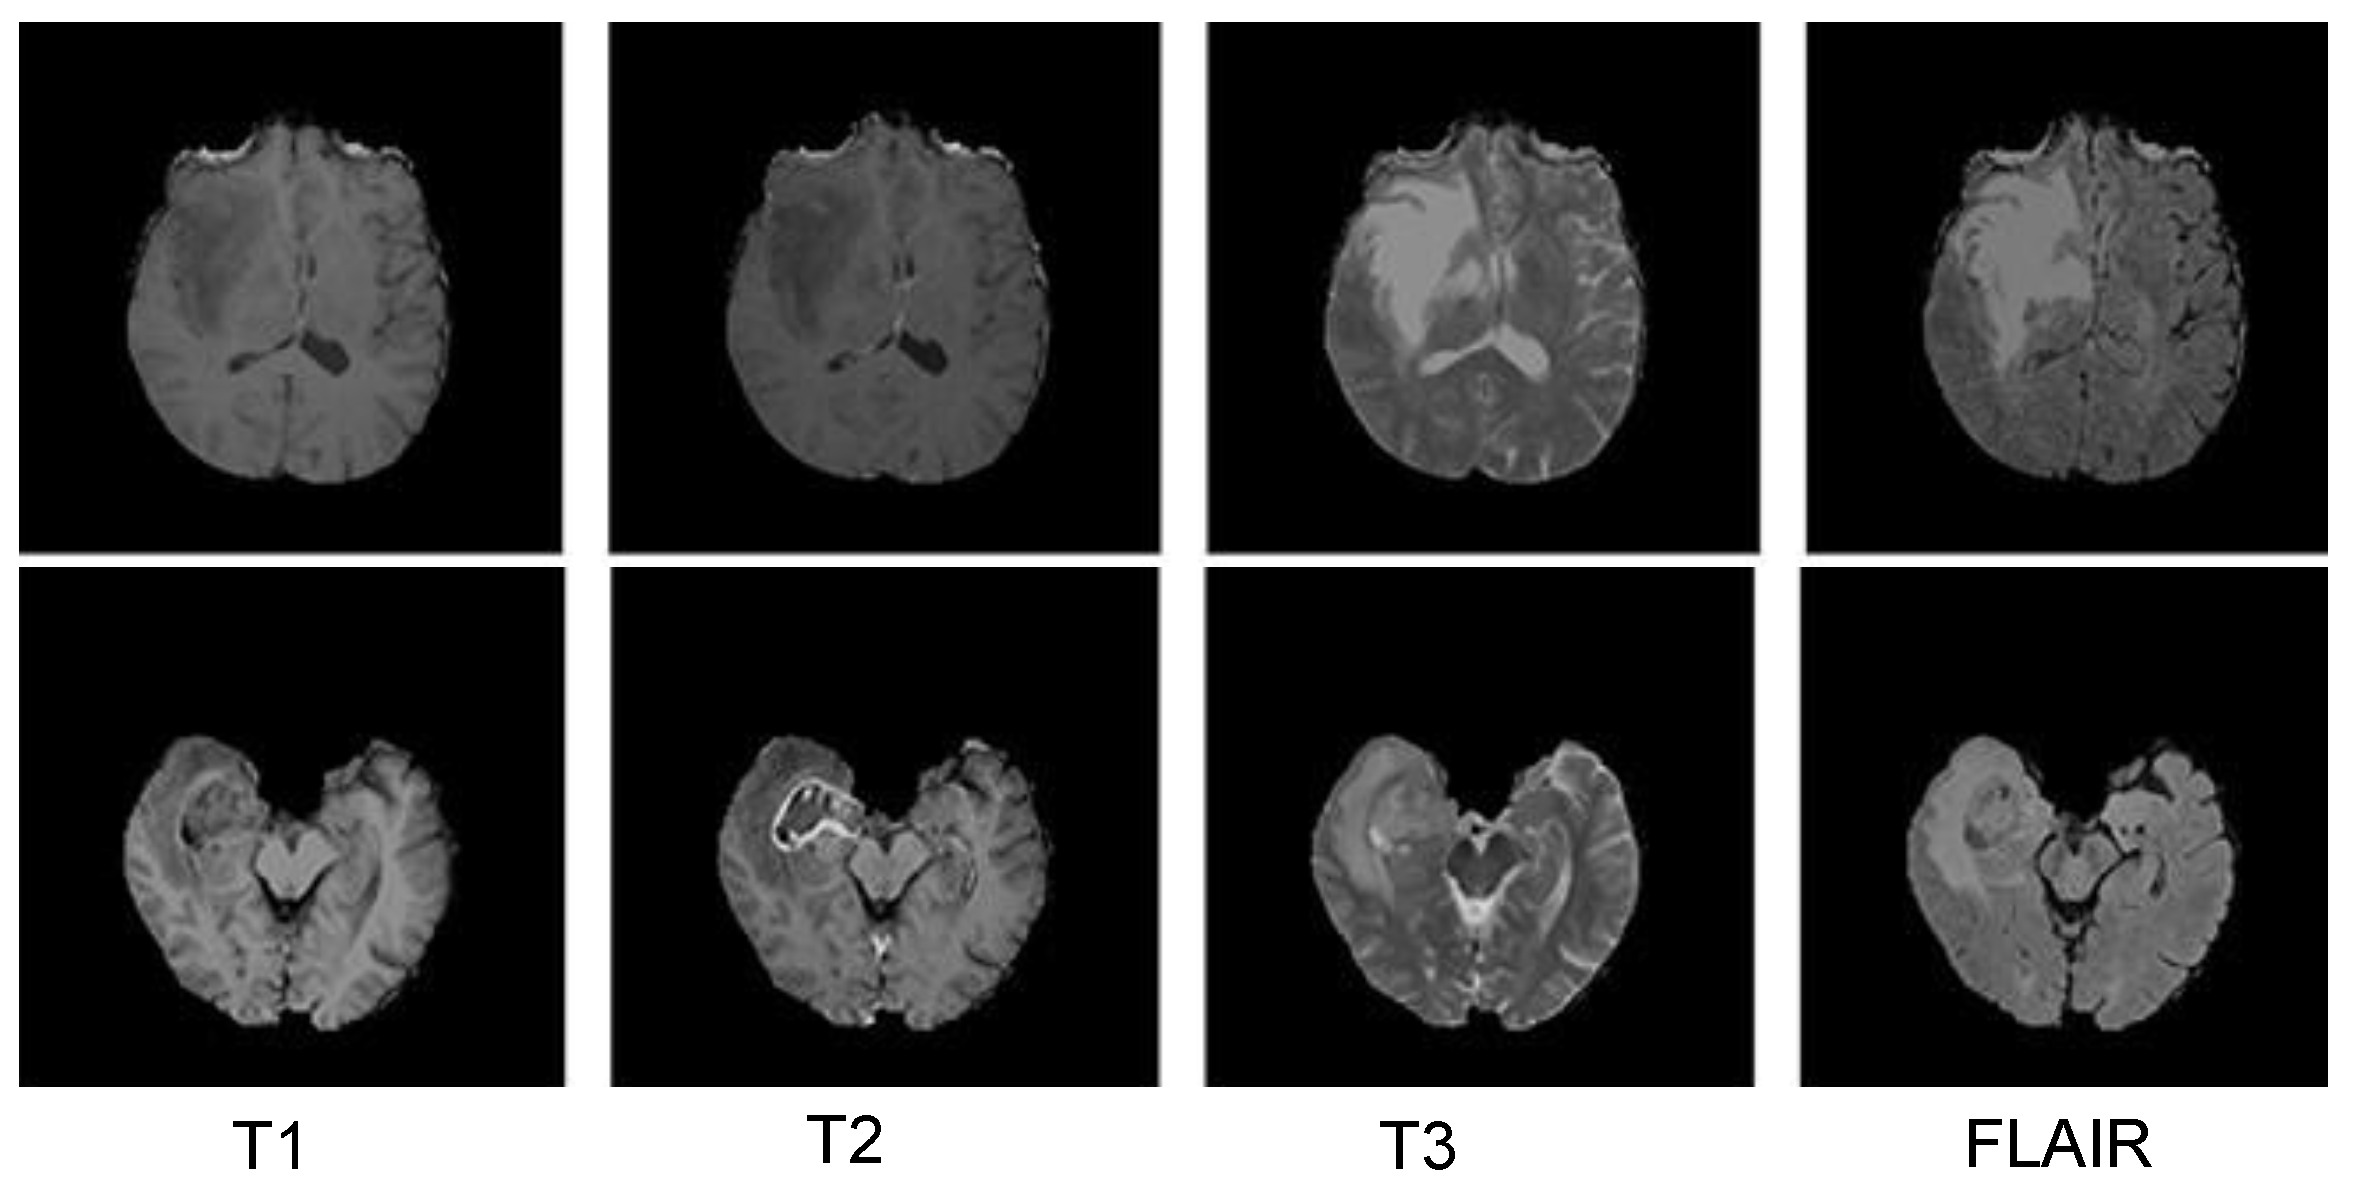

3.5.1. BraTS 2018 Dataset